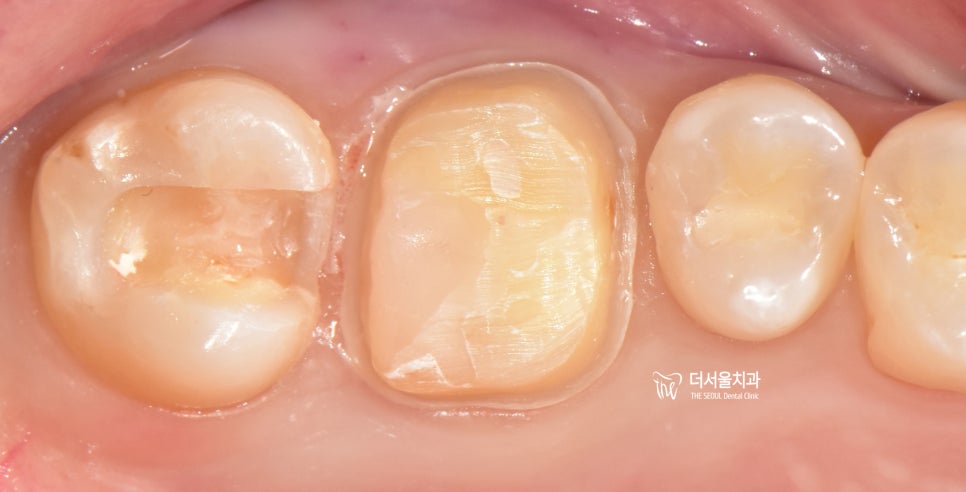

4. 구강 내 사진으로 보는 치료 과정

눈으로 봤을 때는

‘이게 충치라고?’ 할 수 있습니다.

근데 교익 방사선 사진에서는

치아 우식증이라는 것을 알 수 있었죠.

해당 부위에 우식증을 제거하면

제거 된 형태 그대로 나오게 됩니다.

물론, 사진을 기준으로 좌측에 있는

치아는 충치의 범위가 크지 않아서

세라믹 인레이로 진행을 하기로 했고,

그 앞에 있는 치아는 썩은 부위가

넓어서 크라운으로 진행하기로

결정 내렸습니다.

그래서, 크라운이 올라가야 되는

자리를 둥근 기둥 형태로 만들엇죠.

이후, 세라믹 인레이와

지르코니아 크라운이 올라간 모습입니다.